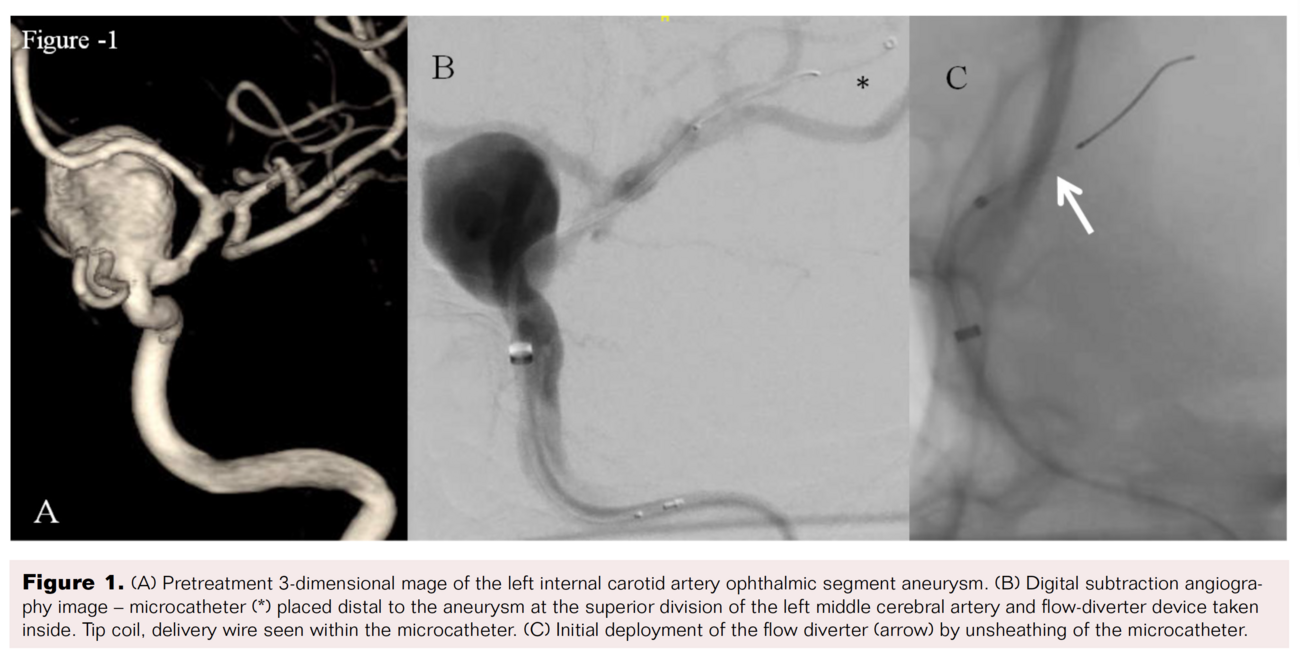

1. After deployment of the Pipeline stent, we encountered many difficulties trying to recapture the delivery wire while attempting to resheath it. It took a moment to realize that the distal tip of the catheter had gotten stuck between the distal marker and the polytetrafluoroethylene (PTFE) sleeve. Meanwhile, we applied reasonable pull force and maneuvered the catheter to recapture the delivery wire (Figure 2).

2. Wire fracture proximal to the proximal marker was recognized by the inability to navigate and the unresponsiveness of the distal delivery wire during torquing and subsequent withdrawal of the wire (Figure 3).

4. Microsnare (Amplatz Goose Neck Snare Kit, comprising 4 mm Loop Snare with true 90° angle, 2.3-3.0 Fr Goose Neck snare catheter) was inserted to pull out the fractured wire by snaring, but was not successful.

5. Subsequently, a Hyperglide balloon catheter (Medtronic) was advanced through the intermediate catheter and placed distal to the resheathing marker of delivery wire. The entire system was pulled out successfully by sandwiching the delivery wire between the inflated balloon and intermediate catheter lumen (Figure 2 and Figure 4).